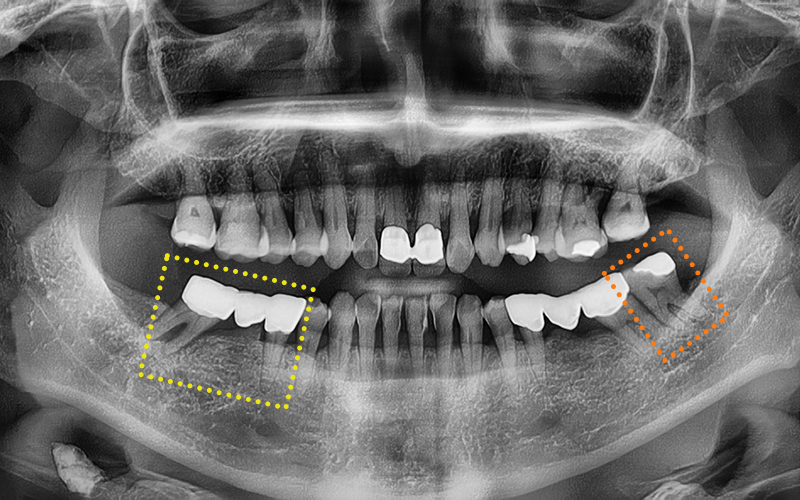

🦷 내원 당시 상태 요약

✔ 우측 아래 첫번째 큰 어금니는

이미 발치된 상태

✔ 우측 아래 두번째 큰 어금니는

치아 파절로 보존 어려워 발치 결정

✔ 두번째 작은 어금니는

기존에 크라운이 씌워져 있었고,

두번째 큰 어금니와

연결된 브릿지 상태였음

✔ 좌측 아래 사랑니는

염증으로 인해 발치 필요

🔍 치료 계획 및 진행 과정